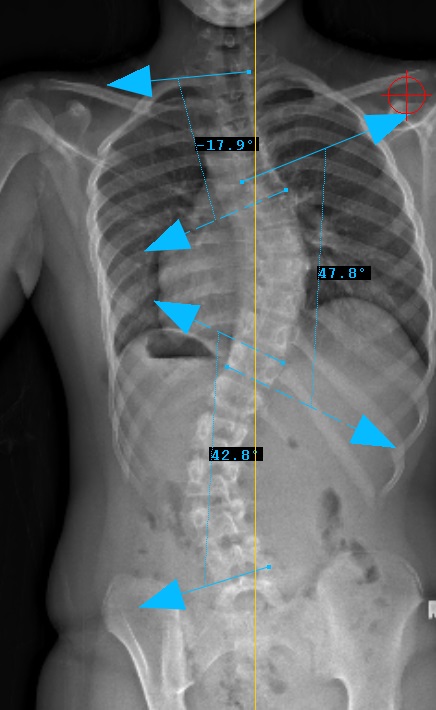

Preop: 1C- Examples

Preop PA View

Curve Type 1

Thoracic curve major, other curves non-structural (bend out to <25o)

Lumbar modifier C

CSVL does not touch apex of lumbar curve

(apex - L1/2 disc)

STEP 3

Sagittal Modifier ( - )

T5-T12 in the <10o range

Therefore, Classification is Type 1C-